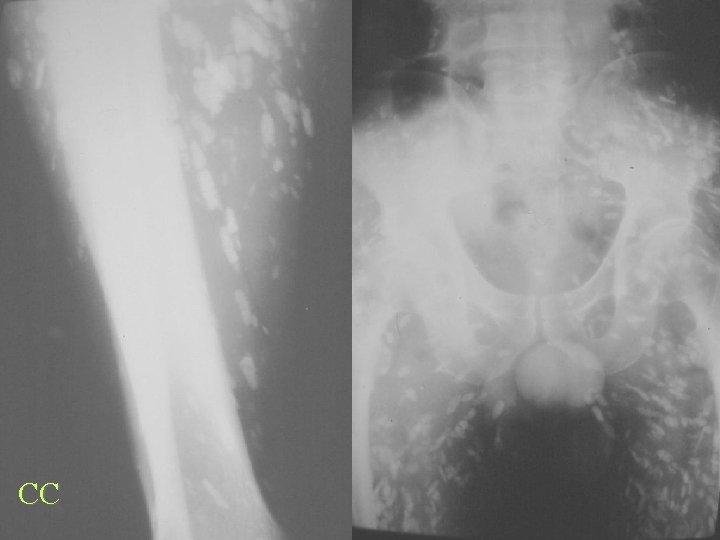

CPPD Flu

CC